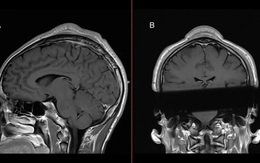

'Mọc sừng' trên đỉnh đầu do nhảy breakdance hơn 20 năm

Một bệnh nhân đã phát triển khối u lành tính trên da đầu sau nhiều năm thực hiện động tác xoay đầu trong nhảy breakdance.